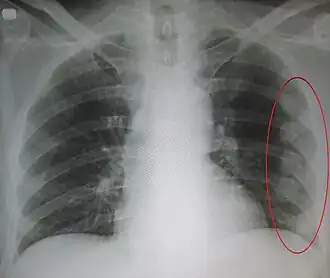

| Um raio-X mostrando múltiplas costelas quebradas do lado esquerdo da pessoa conforme marcado pela oval | |